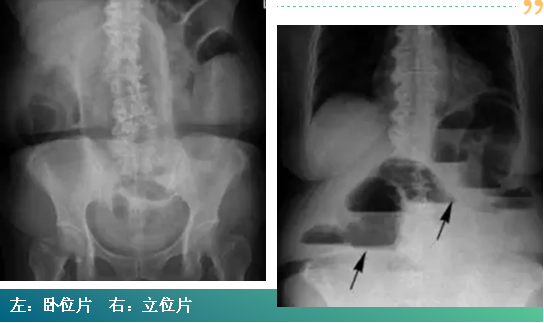

肠梗阻是最常见的急腹症之一,这两张图片是同一名患者,图左是肠梗阻腹部卧位片,图右是肠梗阻腹部立位片。从卧位片上看并没有征象表明该患者发生了肠梗阻,但立位片上可以明显看到肠管发生了像楼梯一样的改变(箭头所指),这是气-液平面,是肠梗阻在影像学上的特征表现。